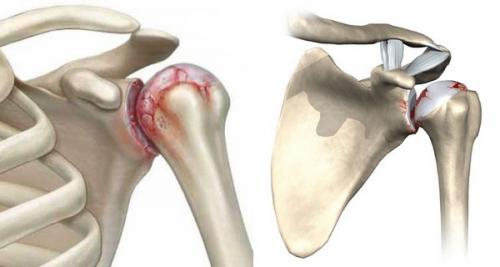

Артроз 2 степени плечевого сустава. Степени артроза

Для каждой степени (стадии) артроза симптомы и лечение имеют свою специфику. Определение степени ДОА плечевого сустава важно для разработки адекватной схемы лечения, рассмотрения вопроса о временной или постоянной нетрудоспособности пациента. При артрозе 2 степени плечевого сустава пациент сохраняет трудоспособность, хотя многие привычные операции требуют значительных усилий и причиняют дискомфорт. Пациентам, у которых плечевой артроз достиг 3 степени, может быть присвоена 3 группа инвалидности, если ограничение подвижности руки препятствует выполнению их должностных обязанностей. При определении стадии артроза специалисты опираются на клинические симптомы и рентгенологические признаки.

При артрозе плечевого сустава симптомы постепенно становятся все более выраженными.

- Для 1 стадии характерны слабая ноющая боль в плече, которая возникает при попытках завести руку за спину, коснуться лопатки, а также после продолжительной нагрузки. В начале движений отмечается умеренная тугоподвижность, которая быстро проходит. Временами движения сопровождаются легким хрустом.

- Вторая стадия проявляется выраженными, достаточно продолжительными болями, которые возникают в ответ даже на незначительную нагрузку. Движения сопровождаются отчетливым хрустом, щелчками, их амплитуда ограничена. Часто появляются признаки синовита.

- На 3 стадии боль интенсивная, практически непрерывная. Движения в суставе сильно ограничены, сопровождаются грубым хрустом. На спине в области соединения головки плечевой кости с суставной впадиной лопатки виден выступ – следствие деформации суставных краев костей.

Рентгенологические критерии:

- 1 степень – незначительное сужение суставной щели, начальные остеофиты в виде заострения краев суставных поверхностей;

- остеоартроз 2 степени проявляется сужением суставной щели наполовину и больше, разрастанием остеофитов, появлением уплотнений (остеосклероза) и кист в подхрящевом (субхондральном) отделе костей;

- для 3 стадии характерны выраженный остеофитоз и остеосклероз, кистоподобные полости в субхондральной костной ткани, практически полное закрытие суставного просвета, свободные тела (суставные мыши) в полости.

Некоторые исследователи выделяют 0 стадию артроза, при которой рентгенологические признаки отсутствуют.